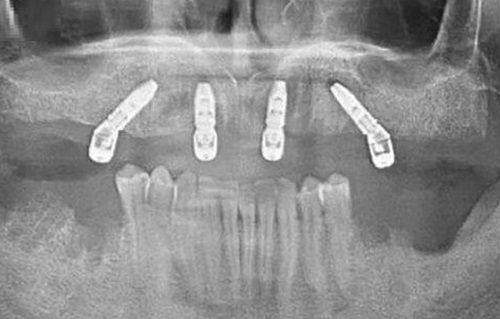

无论是常见的牙齿清洁、补牙,还是复杂的牙齿矫正、种植牙手术,齐美口腔的医生们都能游刃有余地应对。他们紧跟口腔医学的发展趋势,不断学习和掌握全新的治疗技术,为患者提供良好质的口腔医疗服务。有了这样专精的医生团队,你还会担心看牙的成效吗?